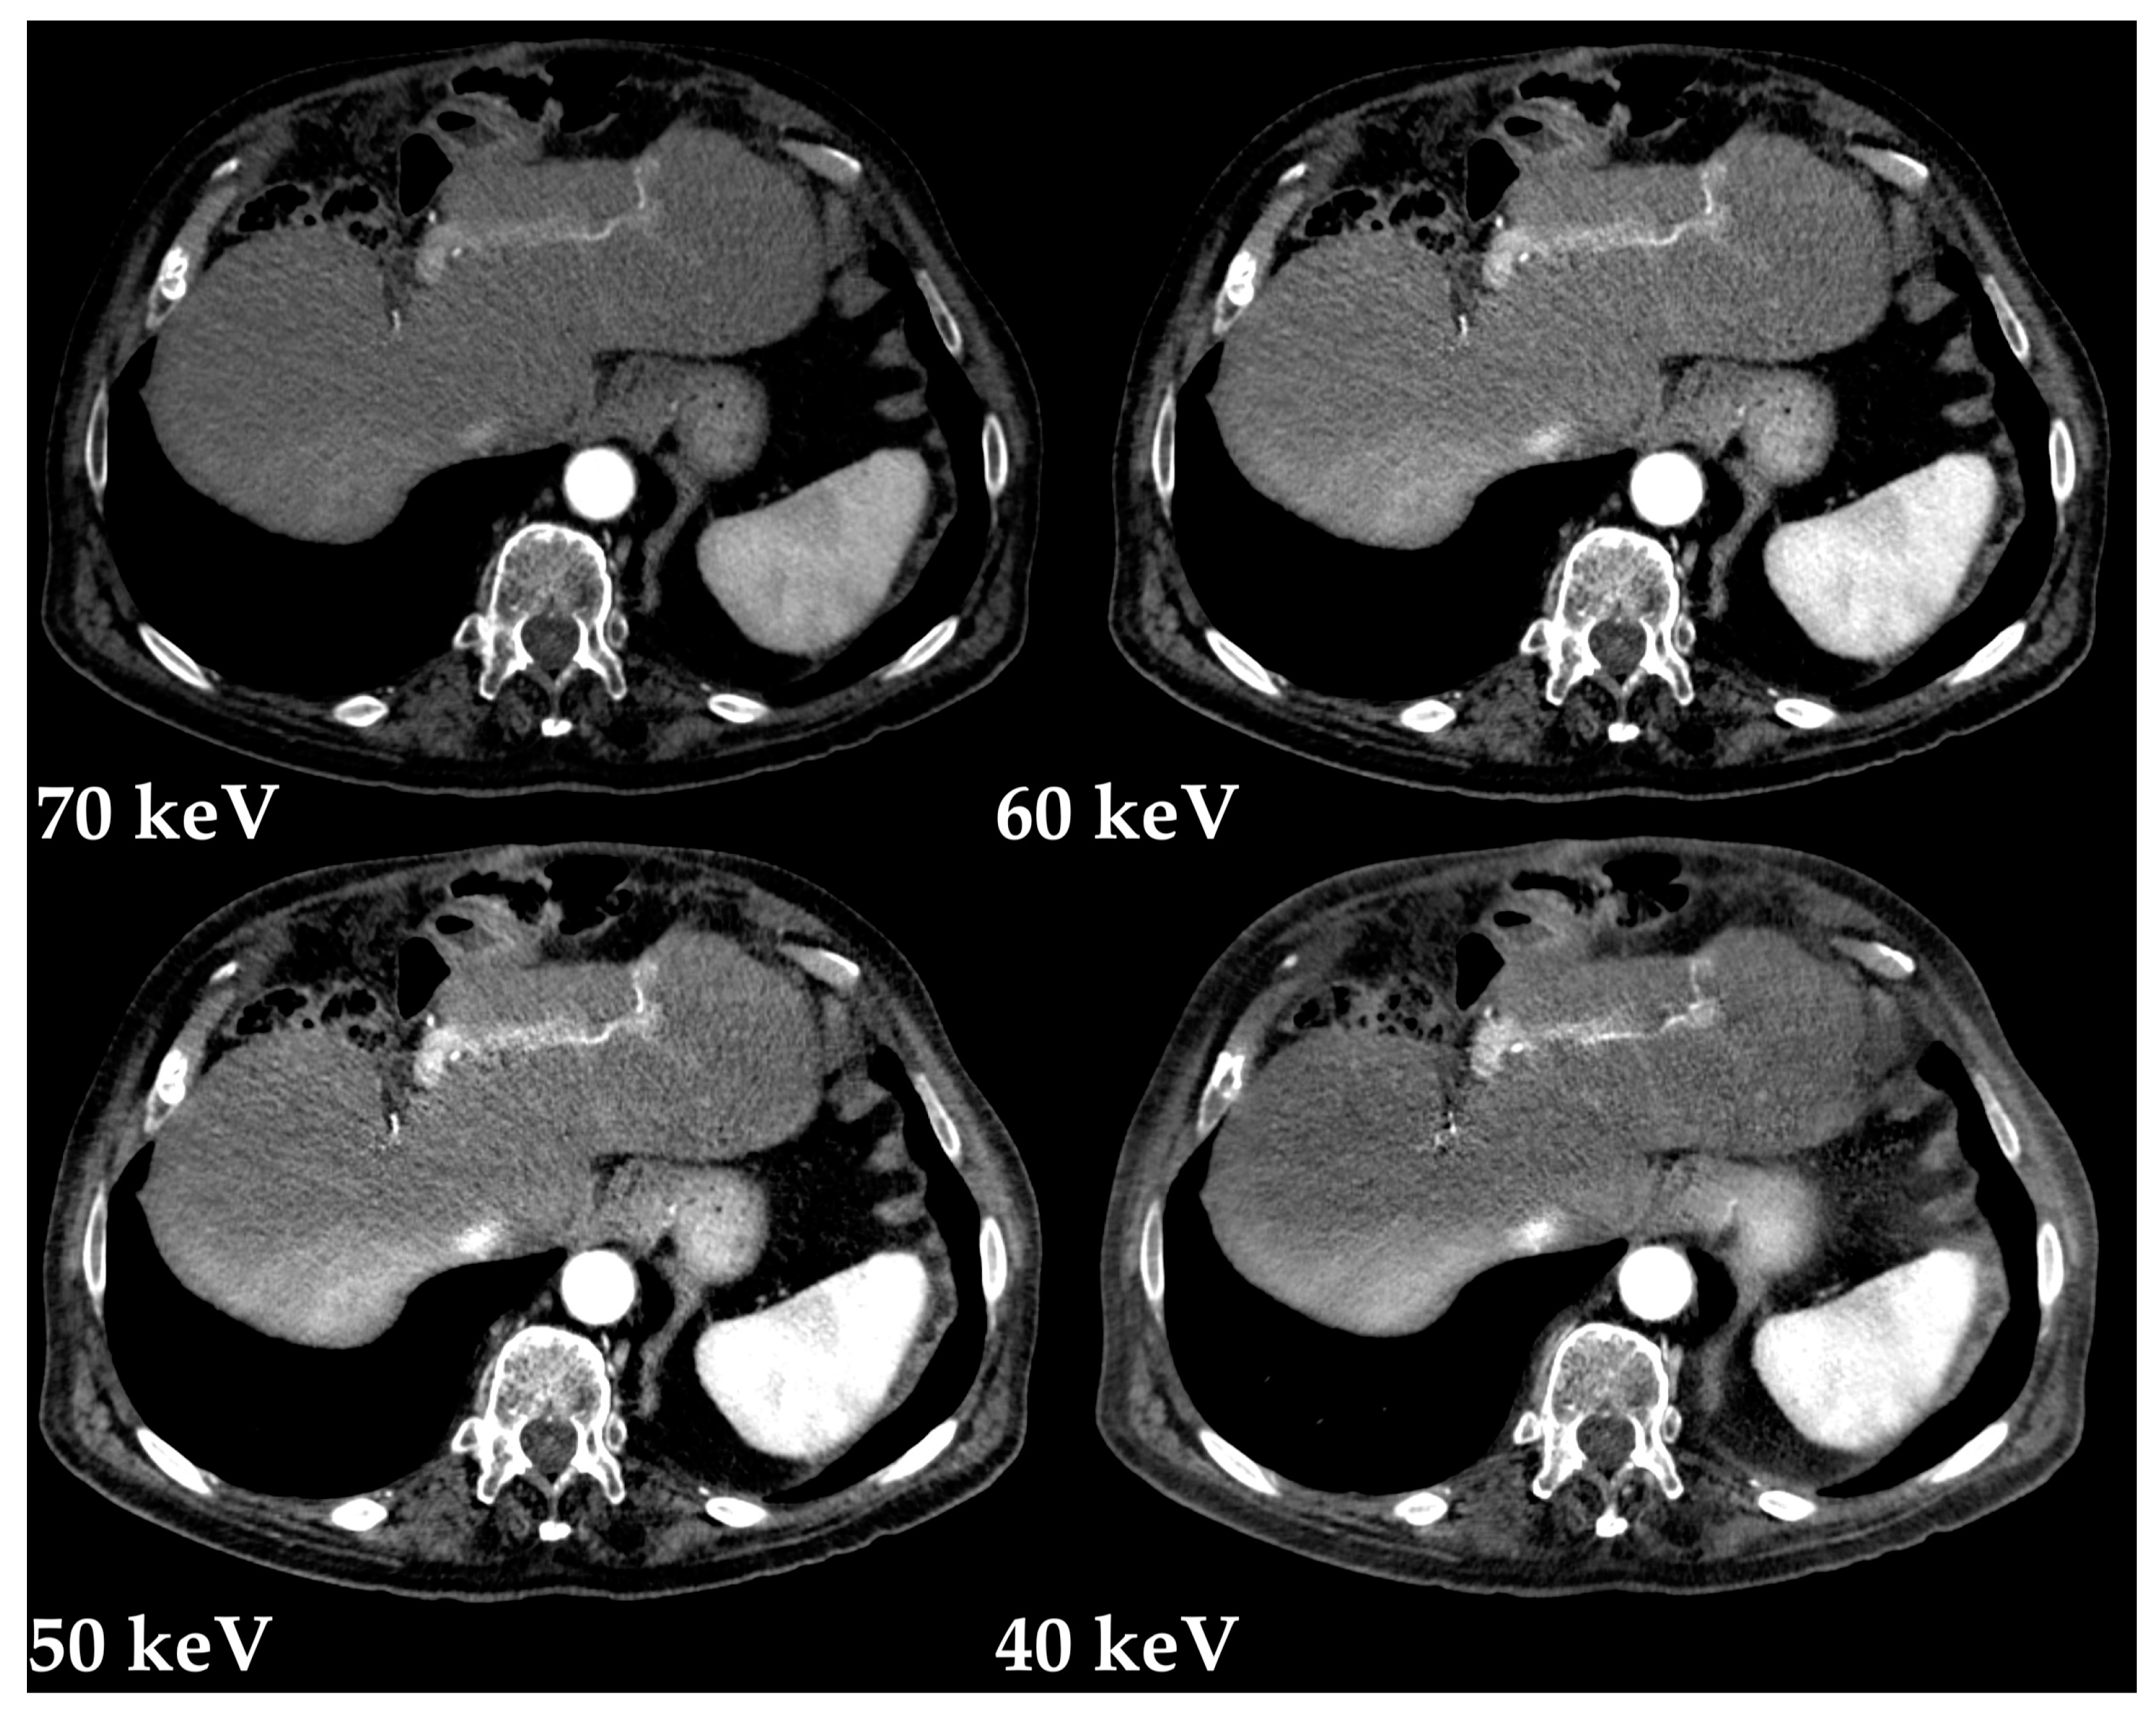

- Große Hokamp, N.; Höink, A.J.; Doerner, J.; Jordan, D.W.; Pahn, G.; Persigehl, T.; Maintz, D.; Haneder, S. Assessment of arterially hyper-enhancing liver lesions using virtual monoenergetic images from spectral detector CT: Phantom and patient experience. Abdom. Radiol. 2018, 43, 2066–2074. [Google Scholar] [CrossRef]

- Shuman, W.P.; Green, D.E.; Busey, J.M.; Mitsumori, L.M.; Choi, E.; Koprowicz, K.M.; Kanal, K.M. Dual-energy liver CT: Effect of monochromatic imaging on lesion detection, conspicuity, and contrast-to-noise ratio of hypervascular lesions on late arterial phase. Am. J. Roentgenol. 2014, 203, 601–606. [Google Scholar] [CrossRef]

- Mileto, A.; Nelson, R.C.; Samei, E.; Choudhury, K.R.; Jaffe, T.A.; Wilson, J.M.; Marin, D. Dual-energy MDCT in hypervascular liver tumors: Effect of body size on selection of the optimal monochromatic energy level. Am. J. Roentgenol. 2014, 203, 1257–1264. [Google Scholar] [CrossRef]

- De Cecco, C.N.; Caruso, D.; Schoepf, U.J.; De Santis, D.; Muscogiuri, G.; Albrecht, M.H.; Meinel, F.G.; Wichmann, J.L.; Burchett, P.F.; Varga-Szemes, A.; et al. A noise-optimized virtual monoenergetic reconstruction algorithm improves the diagnostic accuracy of late hepatic arterial phase dual-energy CT for the detection of hypervascular liver lesions. Eur. Radiol. 2018, 28, 3393–3404. [Google Scholar] [CrossRef]

- Marin, D.; Ramirez-Giraldo, J.C.; Gupta, S.; Fu, W.; Stinnett, S.S.; Mileto, A.; Bellini, D.; Patel, B.; Samei, E.; Nelson, R.C. Effect of a Noise-Optimized Second-Generation Monoenergetic Algorithm on Image Noise and Conspicuity of Hypervascular Liver Tumors: An In Vitro and In Vivo Study. Am. J. Roentgenol. 2016, 206, 1222–1232. [Google Scholar] [CrossRef]